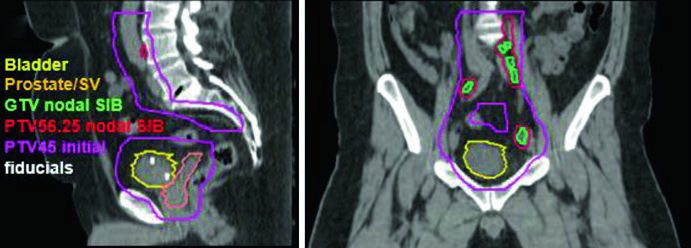

Enfermedad Ganglionar Positiva: Boost Integrado Simultáneo

Los pacientes con ganglios positivos representan un escenario terapéutico diferenciado. La fase inicial puede incorporar un boost integrado simultáneo (SIB) para escalar la dosis en la adenopatía macroscópica. La dosis SIB recomendada es de 5625 cGy en 25 fracciones diarias (225 cGy/fracción), dirigida a la enfermedad ganglionar macroscópica con PTV = GTV + margen de 5 mm, respetando la tolerancia de tejidos normales adyacentes.

El caso clínico ilustrado corresponde a un varón de 51 años con carcinoma urotelial cT2N+ localmente avanzado, con masa de 5,0 x 2,8 cm en la pared posterolateral izquierda, sometido a TURBT máxima. Las imágenes de planificación sagital y coronal demuestran cómo el PTV del SIB nodal (PTV 56,25) se superpone al campo pélvico inicial (PTV 45) sin comprometer excesivamente las estructuras adyacentes, con los fiduciales claramente visibles en el lecho de TURBT. En la fase de boost, el volumen se reduce al lecho de TURBT con margen conformado, permitiendo escalamiento seguro de dosis al tumor primario.